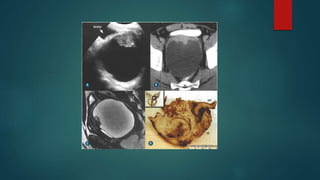

CISTOADENOCARCINOMA